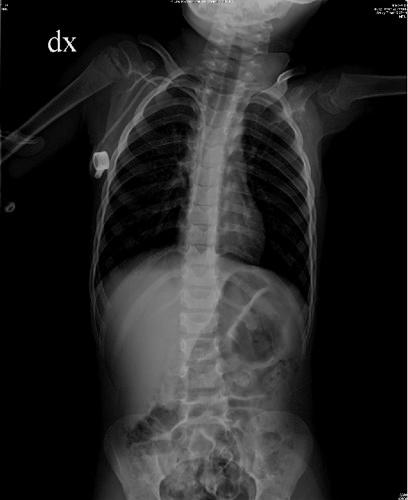

Progress in medical and scientific research has increased the chances of survival for young patients with congenital diseases, children who, in the past, would not have had any chance of survival. Nowadays, congenital diseases can be treated with appropriate replacement therapies. These treatments can be difficult to administer in young patients because of the high frequency of administration (sometimes more than a dose per week), the use of intravenous infusion and the long-term or life-term requirement.

医学和科学研究的进展提高了患有先天性疾病的年轻患者的存活几率,这些儿童在过去没有任何存活的机会。如今,先天性疾病可以通过适当的替代疗法进行治疗。由于给药频率高(有时每周超过一剂)、使用静脉输液以及长期或终身需求,这些治疗在年轻患者中可能难以实施。